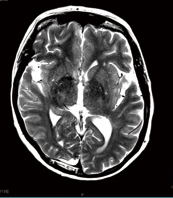

美国纪念斯隆凯特琳癌症中心Kotecha等纳入近70项临床试验的回顾性分析显示,每20例转移性肾细胞癌(RCC)患者中约有1例为无症状性脑转移。近1600例患者接受了评估,其中4.5%…